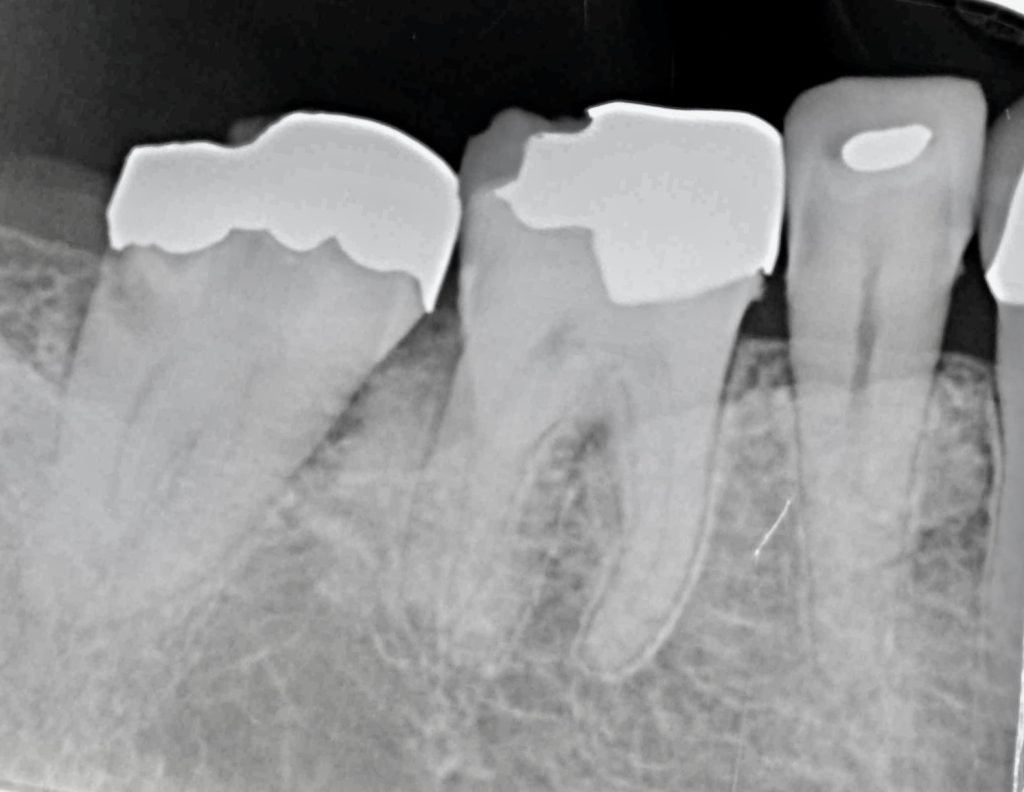

成人のカリエスの大部分の原因は隣接面カリエスと言われており、デンタルフロスや歯間ブラシでプラークコントロールを行う事で重要です。

今回、古いメタルインレーの中でカリエスが進行し、骨縁下まで進行していました。

抜歯と同時にインプラント埋入手術を行い、4ヶ月ほどで治療を完了いたしました。